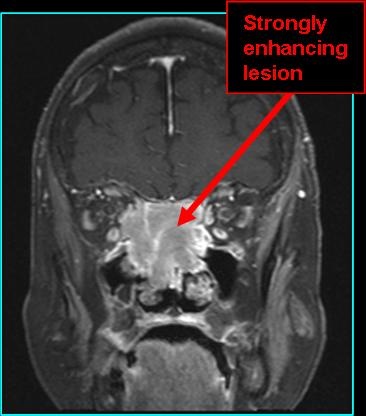

- On MR:

- T1 post-contrast: moderate enhancement